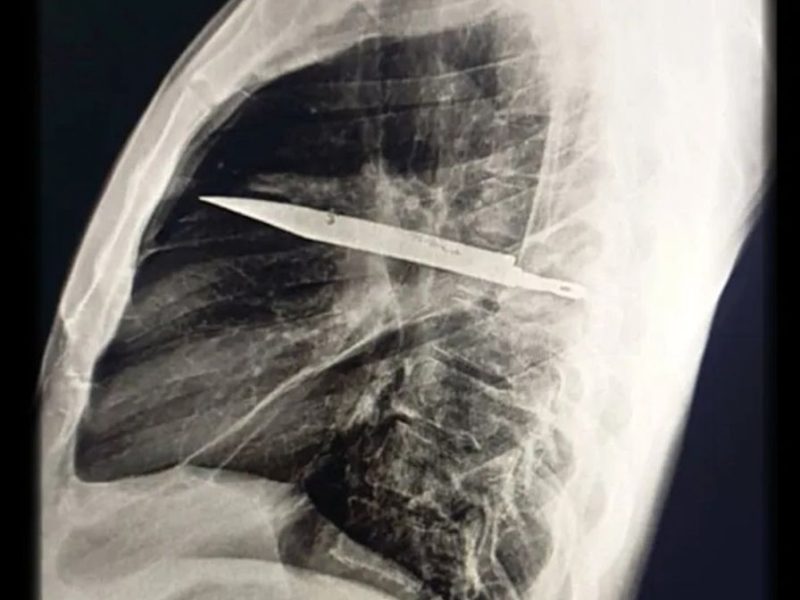

این سیتیاسکن (سمت چپ) تیغه چاقوی باقیمانده در سینه مرد را نشان میدهد و تصویر سهبعدی بازسازیشده از سیتی قفسه سینه (سمت راست) هم تیغه چاقو و آسیبهای استخوانی مرتبط با آن را نشان میدهد